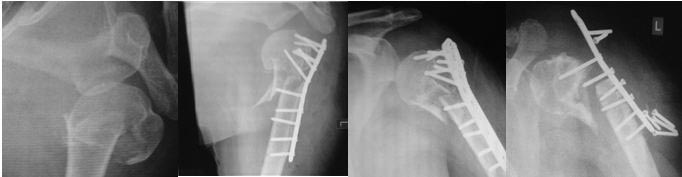

Уважаемые коллеги! Случай из практики. Снимки поразили. Пациентка 56

лет, вколоченный перелом шейки и головки левого плеча. На втором снимке

результат после операции остеосинтеза, на третьем - через два месяца, на

последнем снимке, как написано в описании снимка - отрицательная

динамика после операции остеосинтеза через год. К отрицательной динамике

привели стандартные упражнения, назначенные травматологом после снятия

фиксирующей косынки. Ваше мнение?

На данный момент в нашем лечебном учреждении была проведена операция по

извлечению конструкции. В будущем, по-видимому, операция эндопротезирования.